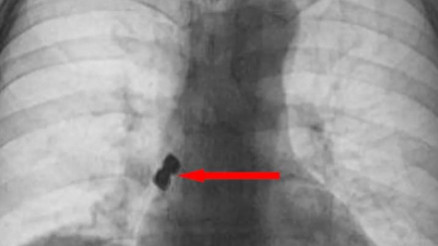

Günümüzde eksik dişlerin yerine konacak protez diş uygulamalarında kullanılan çok değişik materyal ve çeşitli yöntemler var. Dental implantların doğal diş yapısına en uygun alternatif olduğunu vurgulayan Ağız, Diş ve Çene Cerrahisi Uzmanı Yrd. Doç. Dr. Ayşe Yılmaz, implant uygulamasının genellikle muayenehane koşullarında ve lokal anestezi altında yapılabilir olmasının da önemli bir avantaj sağladığına dikkat çekti.

#İmplant DişDoğal dişler, çeşitli nedenlerle kaybedilebilir. Bu boşluklara, implant tedavisiyle, kişinin kendine aitmiş gibi hissedebileceği ‘yeni bir diş’ yapılabilir. Peki, implant tedavisi ne kadar sürer? İmplant yapılırken acı hissedilir mi? Ağız, Diş ve Çene Cerrahisi Uzmanı Dr. Neşe Kahraman, dental implant tedavisiyle ilgili en çok merak edilen soruları yanıtladı.